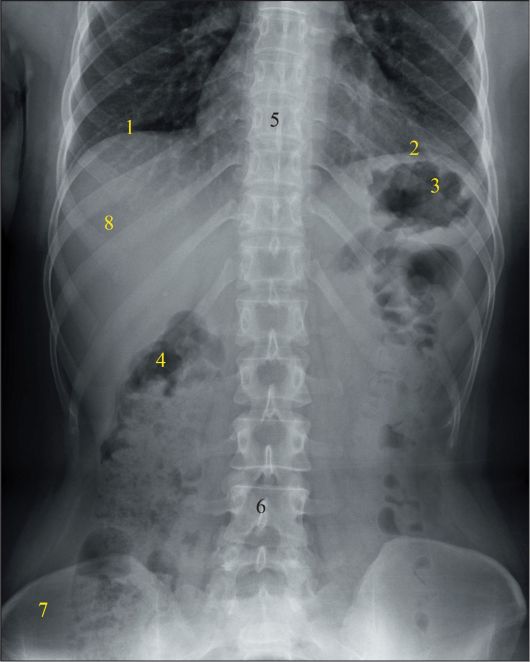

Нормы обзорной рентгенографии брюшной полости